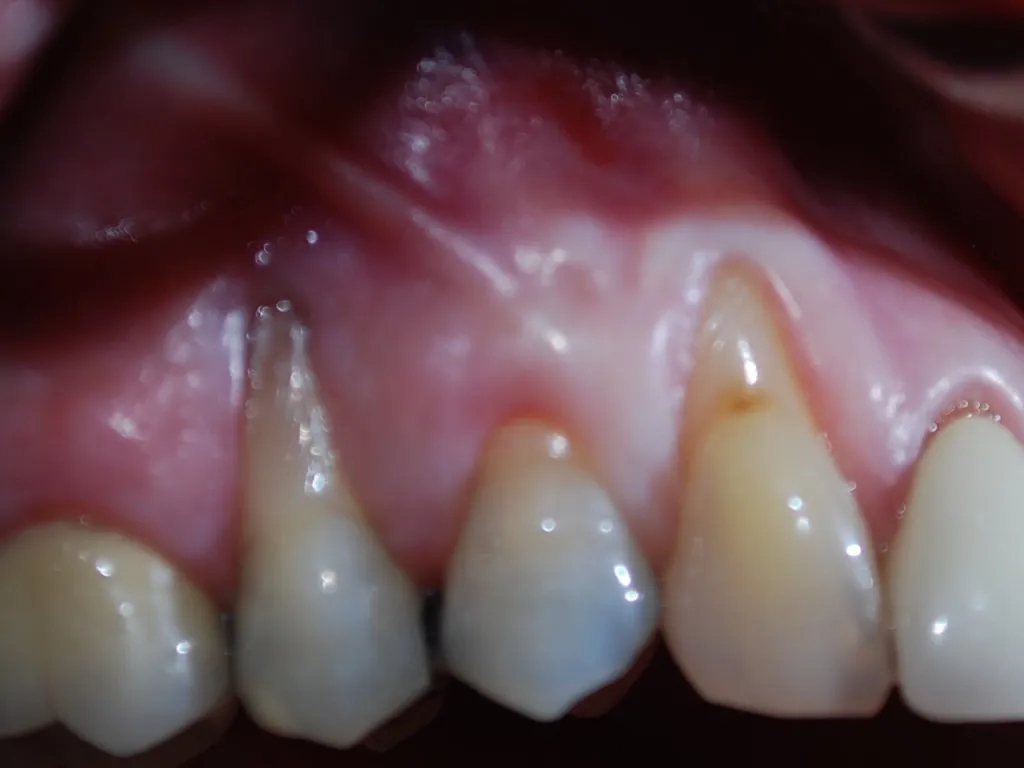

Connective Tissue Gingival Grafting for Gingival Recession